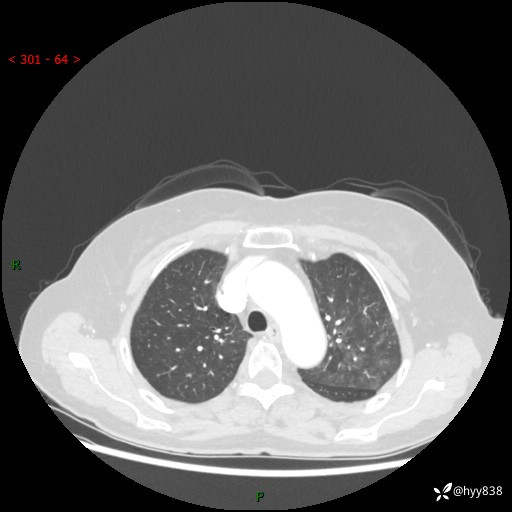

老年女性,偶然发现肺结节10天。结节不大,空洞不小,还牵拉胸膜---结果公布~

胸部CT增强(2024.8.2)